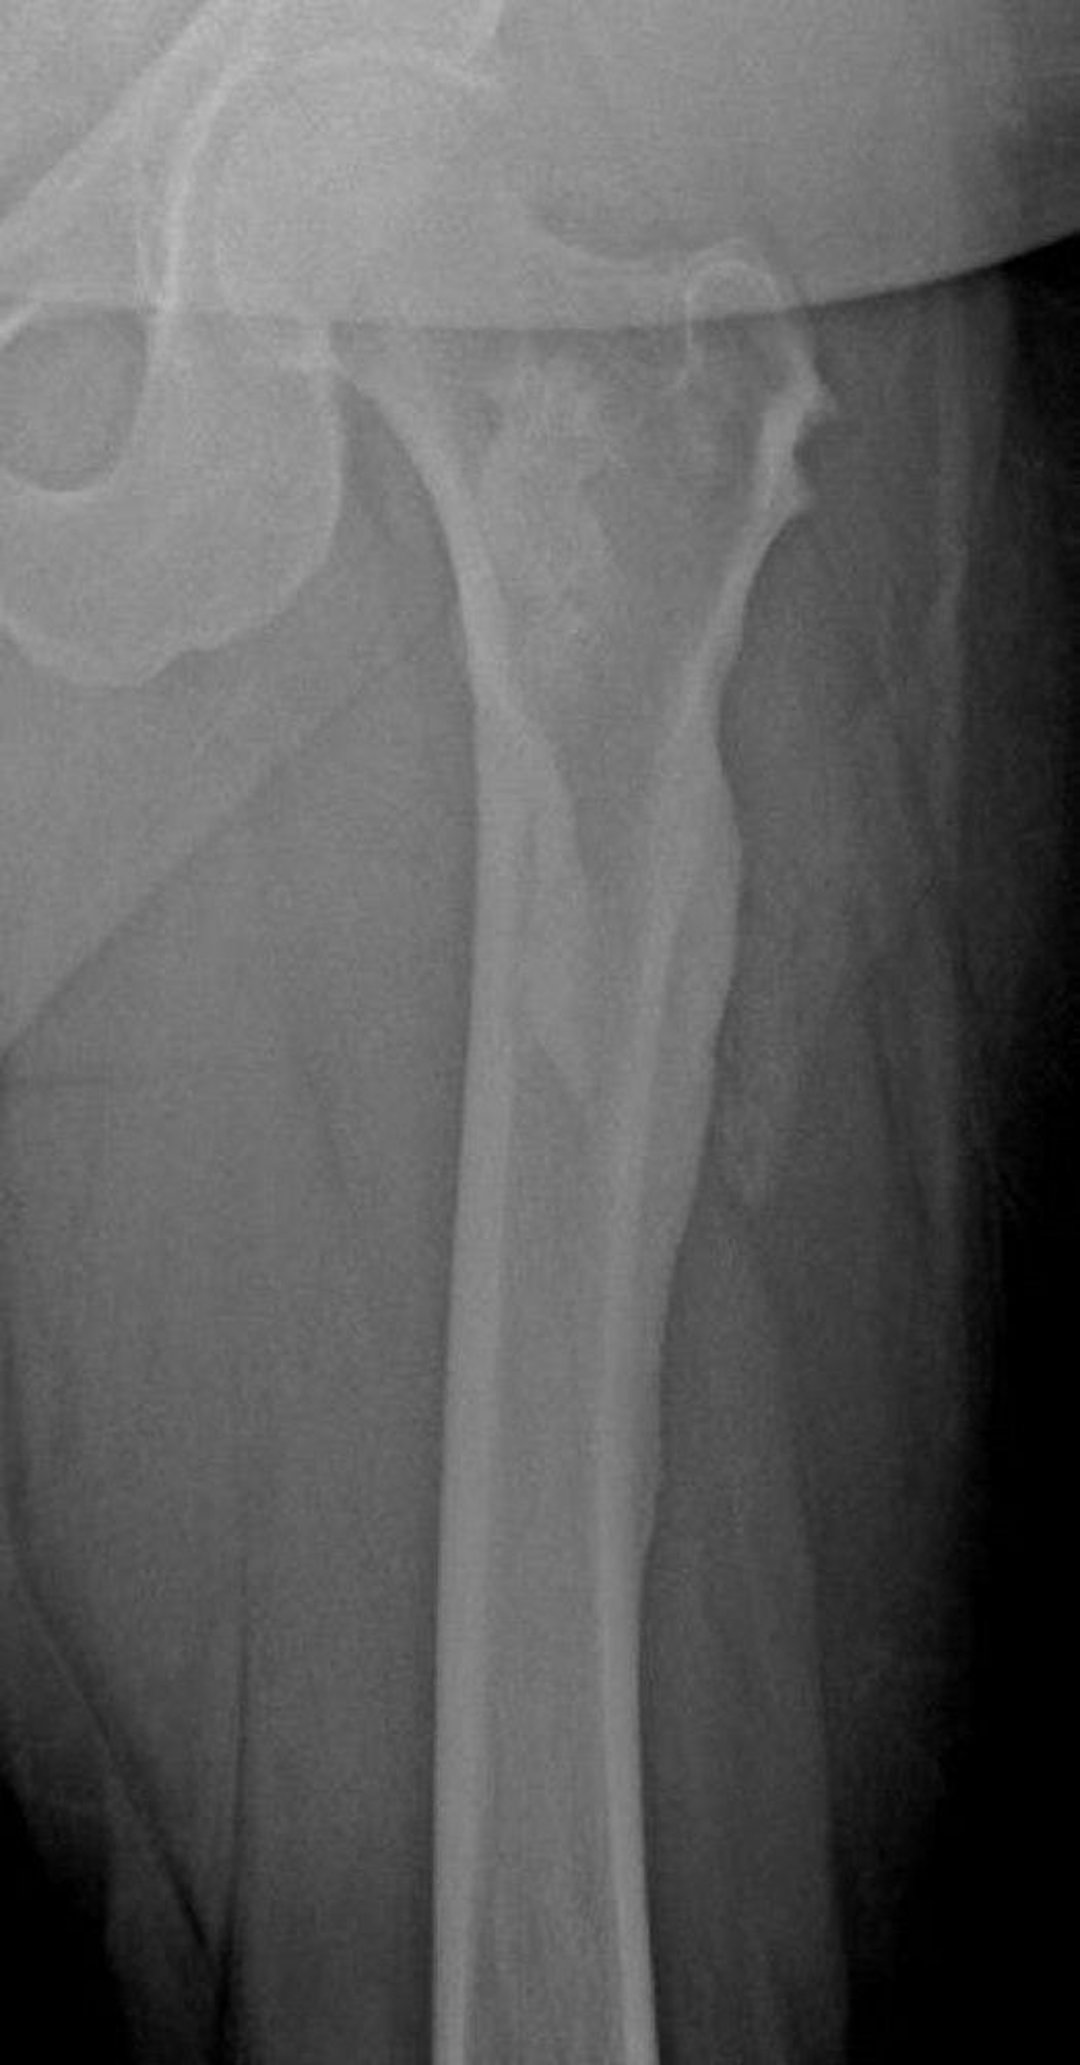

Melorheostosis (Dripping Candle Wax)

This radiograph shows the "dripping candle wax" appearance of melorheostosis in the femur; it is particularly apparent at the lateral femoral cortex.

Image courtesy of Michael J. Joyce, MD, and David M. Joyce, MD.